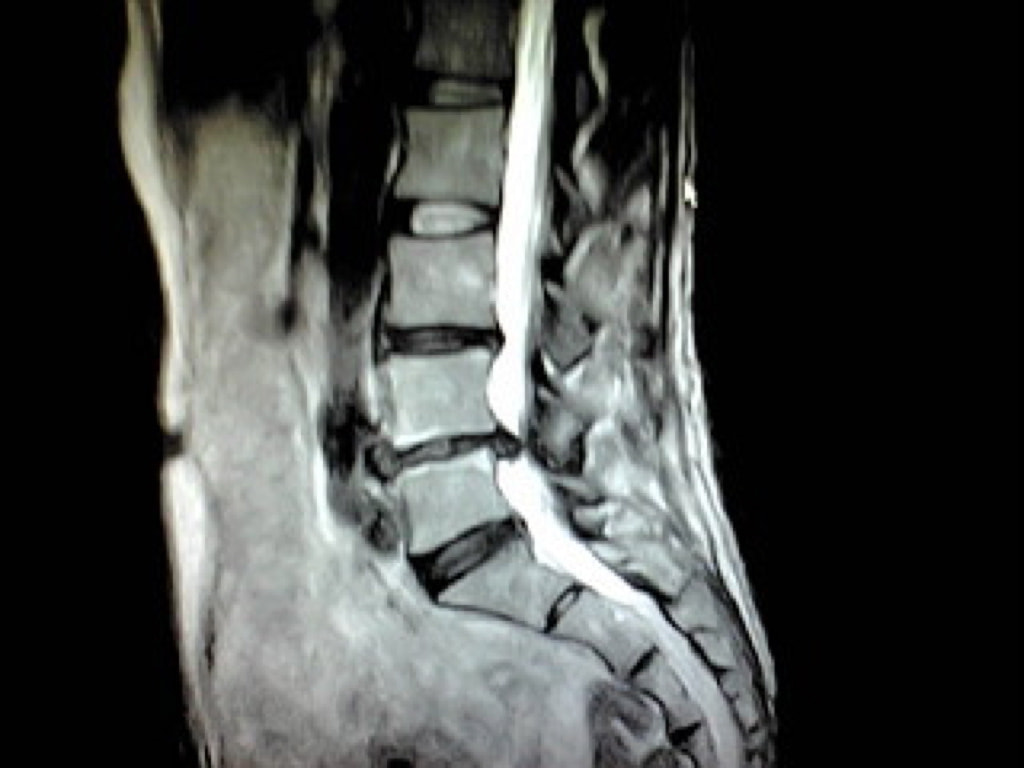

腰椎MRI画像

5|腰椎MRIドック

坐骨神経痛や腰痛の原因となる腰椎椎間板ヘルニアや腰部脊柱管狭窄症などが発生する腰椎を無痛でチェックします。

所要時間:30分  費用:22000円(消費税込み)